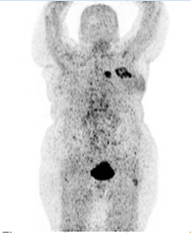

[68Ga] Ga-FAPI PET-CT scan was then performed and the interpretation with comparison to baseline [18F] F-FDG PET -CT scan was done by the same user. The study demonstrated abnormal FAPI uptake in the known left breast tumor and one ipsilateral satellite small chest lesion, both with central areas of no uptake in keeping with necrotic tissue. On low dose CT, the breast tumour measured 5.1 x 5.8 cm (AP X TV) and a satellite mass abutting the sternum measured 2.1 x3 cm (AP x TV) with no underlying bone changes (Figure 3 & 4).

Figure 3: FAPI PET MIP projection showed two lesions in the chest with intense FAPI uptake, one with central area of no FAPI uptake.